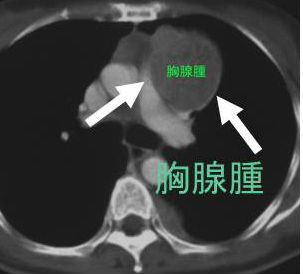

成人になるにつれて退化する胸腺細胞から胸腺腫が発生します。心臓の前上部、前縦隔にできます。

甲状腺超音波(エコー)上、胸腺腫は甲状腺の下に見え、内部不均一な腫瘤で、特徴的な所見に欠きます。小児の胸腺とは異なる見え方です。

心臓の上に乗っかるような形態なので、左に多く、CTで見ると、あたかも甲状腺結節・甲状腺腫瘤・甲状腺腫瘍のように見えます。